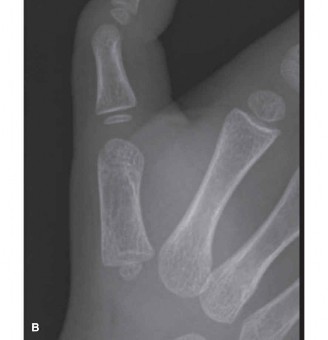

Preoperative evaluation is predominantly clinical. The diagnosis is confirmed by the presence of a palpable Notta's nodule at the volar MCP crease and a fixed or triggering flexion deformity of the IP joint. Advanced imaging, such as ultrasonography or magnetic resonance imaging (MRI), is rarely indicated for classic presentations. However, in atypical cases where a foreign body, anomalous tendon insertion, or mass (e.g., giant cell tumor of the tendon sheath) is suspected, ultrasound can be a cost-effective and non-invasive adjunct to evaluate the morphological characteristics of the FPL tendon and pulley system.